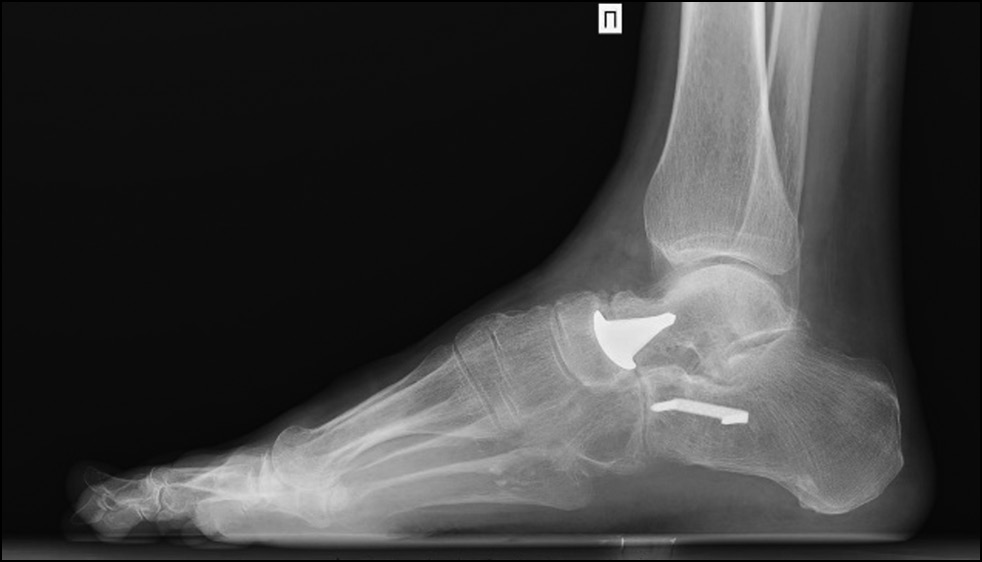

По данным рентгенографии с нагрузкой и компьютерной томографии признаков нестабильности эндопротеза головки таранной кости не отмечено (рис. 10, 11).

Рис. 10. Рентгенограмма правого голеностопного сустава и стопы через 2 года после операции.

Fig. 10. X-ray of the right ankle and foot 2 years after surgery.

Рис. 11. Сагиттальный срез компьютерной томограммы правого голеностопного сустава и стопы через 24 месяца после проведённого лечения: не определяются лизис около ножки эндопротеза, признаки прогрессирования дегенеративных изменений суставной поверхности ладьевидной кости.

Fig. 11. Sagittal section of a CT scan of the right ankle joint and foot 24 months after treatment: no lysis was detected near the leg of the endoprosthesis, no signs of progression of degenerative changes in the articular surface of the scaphoid bone.